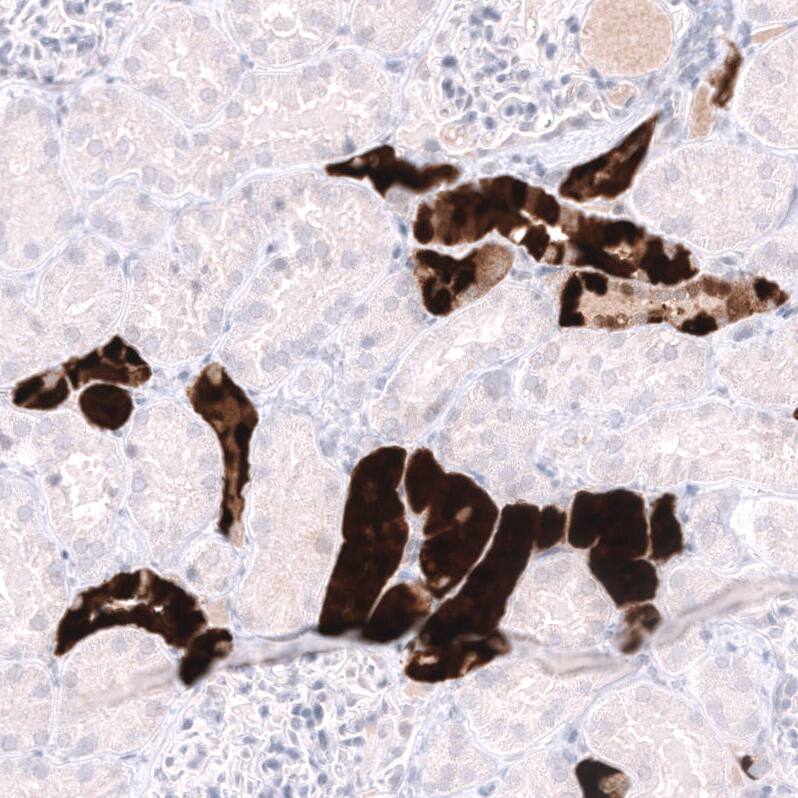

Staining of human kidney shows strong cytoplasmic positivity in cells in tubules.